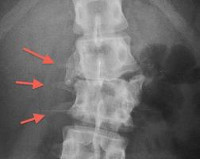

Q67.5 Врожденная деформация позвоночника